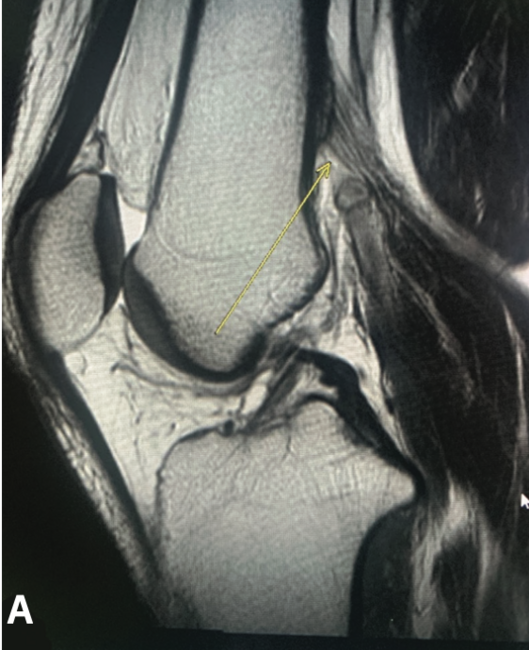

The Important Role of Clinical Suspicion in Diagnosis of Type V Popliteal Artery Entrapment Syndrome

Popliteal artery entrapment syndrome (PAES) is a rare vascular condition typically characterized by an aberrant relationship of the popliteal artery with its surrounding myofascial structures in the popliteal fossa.1,2 It results in compression of the popliteal artery in the popliteal fossa, predominantly during plantarflexion.1-3 PAES primarily affects young adult males without a previous history of cardiovascular risk factors.1-3 As a diagnosis that tends to be missed, the overall incidence of PAES ranges widely from 0.17% to 3.5% in the general population.4-6 Furthermore, 30% of patients with PAES experience bilateral symptoms.7 Patients with PAES typically present with intermittent claudication occurring primarily during exercise and dissipating at rest.1,2 Should PAES be left untreated or go undiagnosed, complications including popliteal artery stenosis (PAS), popliteal artery thrombosis (PAT), and distal arterial thromboembolism (DAT) may occur.1,2 Even though PAES is rare, it is an often overlooked cause of morbidity in this patient cohort. We present a case of PAES in a patient with a prior history of multiple unsuccessful diagnoses and treatments.